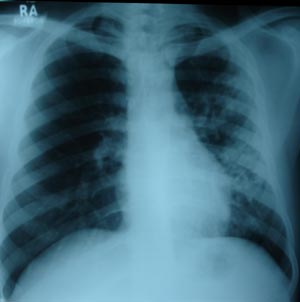

Left mid zone Koch’s infection 5

Right mid zone shows multiple fibronodular opacity, suggestive of unilateral koch’s infiltration. Patient on 4 drug AKT regimen. Marked improvement compared to previous x ray.